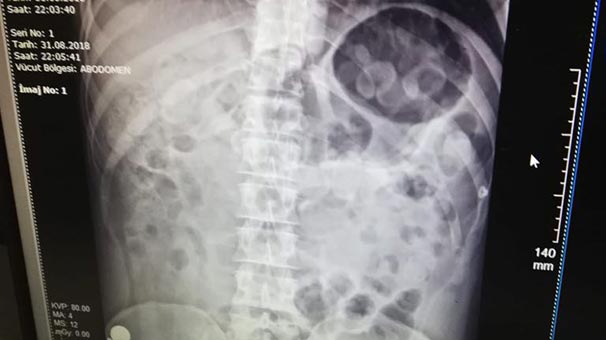

Zanlının hastanede röntgen filmi çekilerek yapılan kontrollerinde, midesinde uyuşturucu taşıdığı anlaşıldı.

Zanlının midesinden istifra yoluyla ve dışkısından siyah elektrik bandına sarılmış kapsül halinde metamfetamin maddesi çıktı.

Toplam 198 gram ağırlığında uyuşturucuyu midesinde sakladığı belirlenen zanlı, gözaltına alınarak Narkotik Suçlarla Mücadele Şube Müdürlüğüne götürüldü.